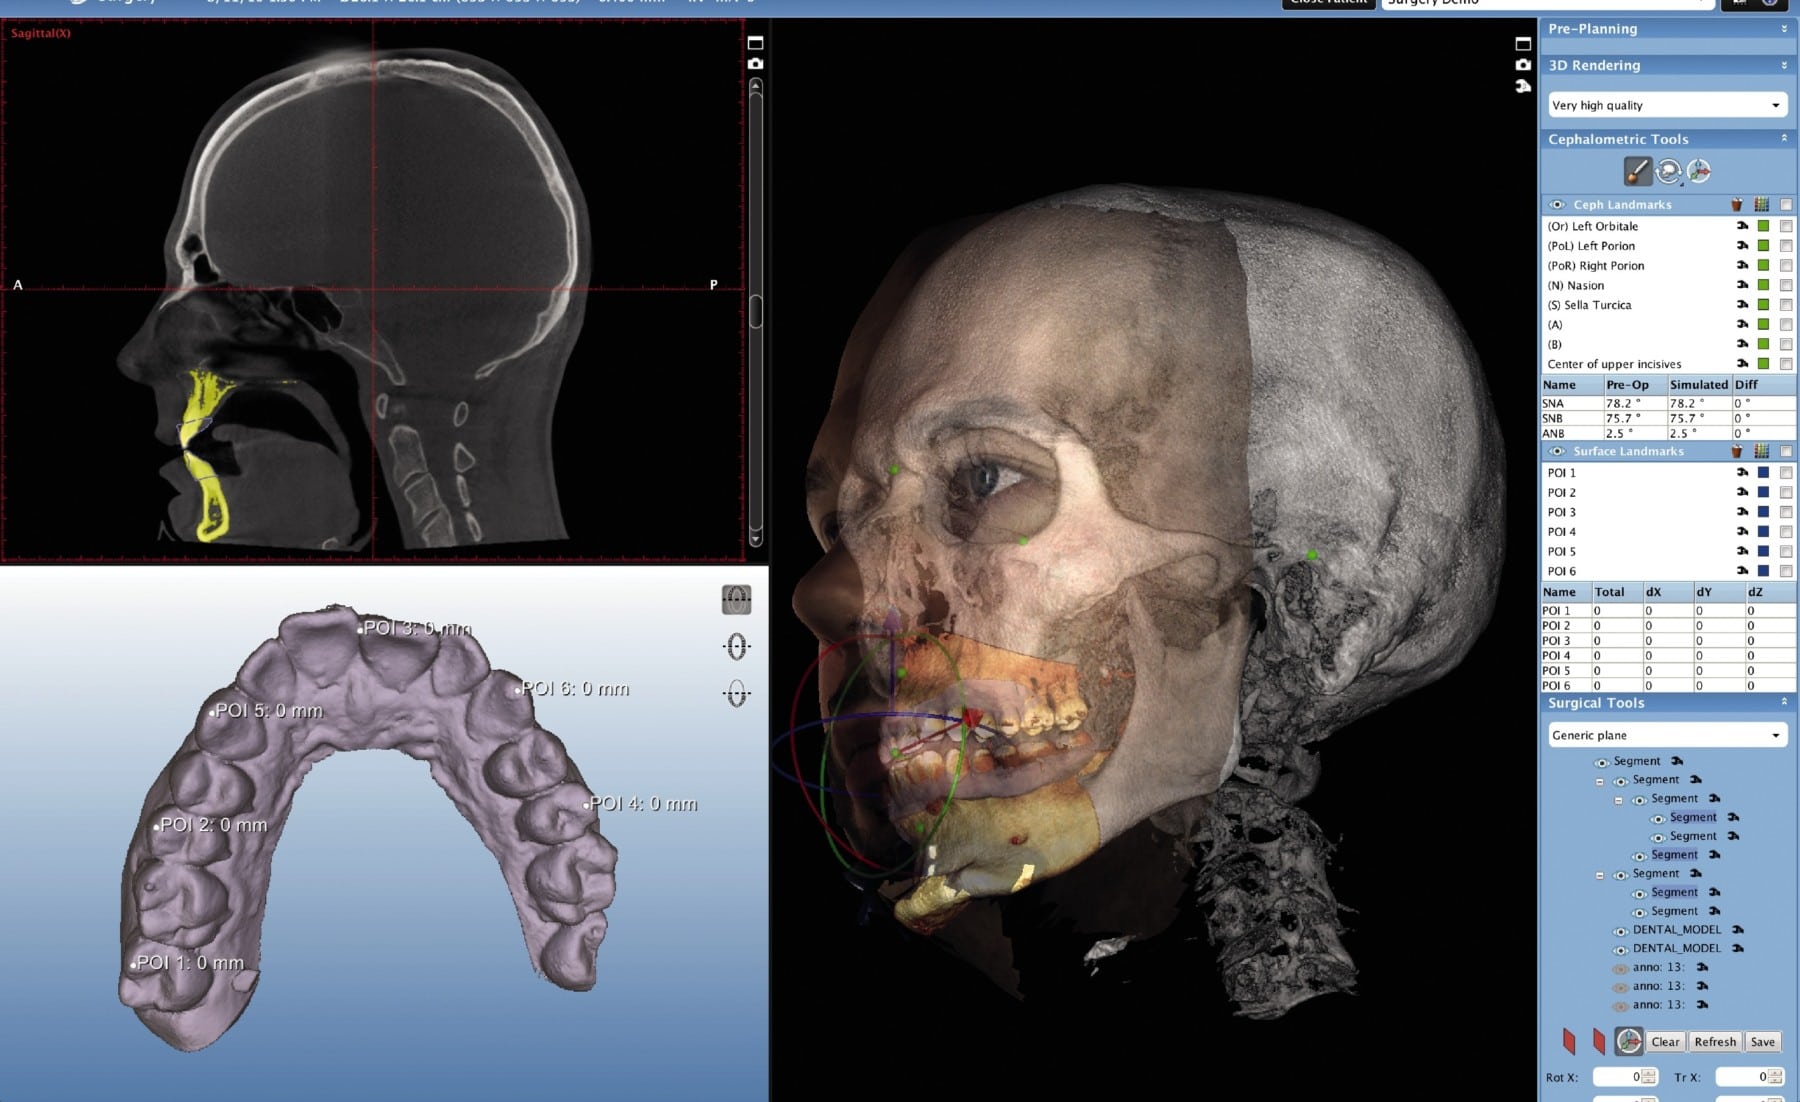

Technical Deep Dive: CBCT Scan Cost Drivers & Engineering Efficacy

1. Core Cost Drivers: Beyond the Sticker Price

2. AI Integration: Quantifiable Workflow ROI

2.1 Pre-Scan Protocol Optimization

Reinforcement Learning (PPO Algorithm) analyzes patient anatomy from preliminary scout views to auto-select:

- Optimal kVp/mAs based on Hounsfield Unit (HU) distribution

- Collimation boundaries via U-Net segmentation of airways/bone

- Rotation speed to minimize motion artifacts (validated against Fourier shell correlation)

2.2 Real-Time Motion Correction

Embedded 3D optical tracking (dual IR cameras) monitors patient movement during scan. Data feeds a Kalman filter that dynamically adjusts:

- Projection weighting in reconstruction matrix

- Temporal smoothing kernels

Clinical Validation: Reduces motion artifacts by 63% (measured via edge sharpness metric on NIST phantom). Eliminates 1.8 retakes/week per unit (average clinic), saving $5,200/year in operational costs.

Digital Dentistry Technical Review 2026: CBCT Integration in Modern Workflows

CBCT integration has evolved from a standalone diagnostic tool to a core workflow engine in 2026. Strategic implementation reduces case turnaround by 18.7% (JDC 2025 Data) but requires architectural foresight. Cost efficiency is no longer determined by scanner acquisition price alone; rather by DICOM data liquidity across CAD/CAM, surgical planning, and practice management systems. Open architecture ecosystems now deliver 31% higher ROI over 3 years versus closed systems (Digital Dental Lab Survey 2025).